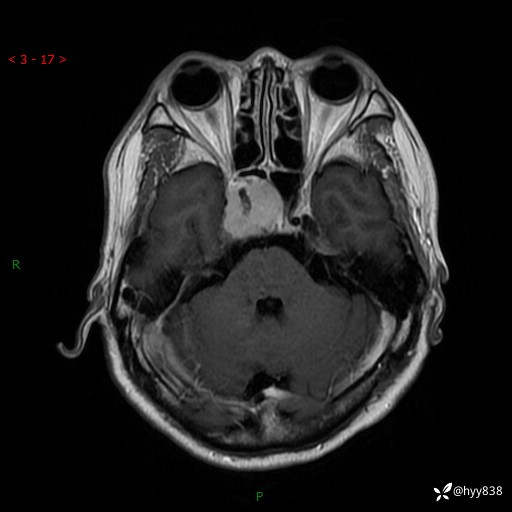

MRI增强(外院平扫)